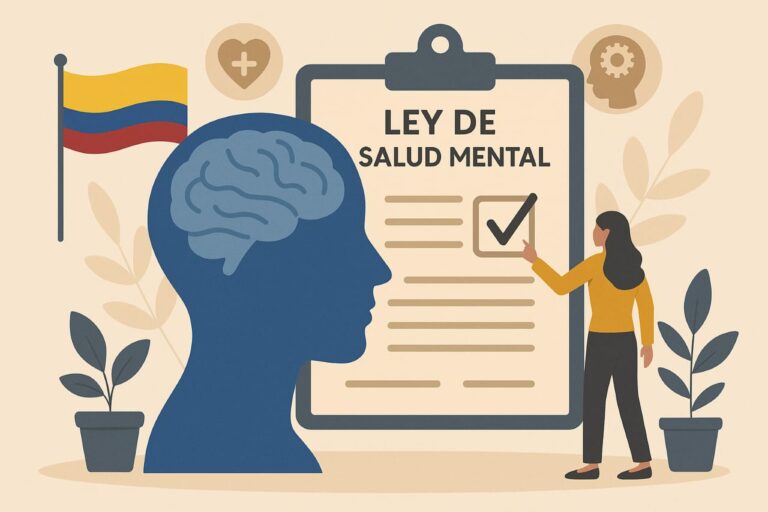

UN HITO EN LA TRANSFORMACIÓN DE LA SALUD MENTAL EN COLOMBIA. Con la promulgación de la...